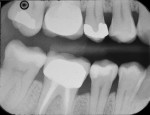

Built off of 13 years of proven PENTA (ie, dipentaerythritol pentaacrylate monophosphate) resin technology from Prime and Bond NT Adhesive, Prime&Bond Elect Universal Adhesive provides a unique micromechanical and chemical bond for long-term success with virtually no postoperative sensitivity. It is ideal in cases where the preparation is primarily in enamel and total-etch technique may be preferred, in preparations with significant exposed dentin where a self-etch technique is warranted, and for preparations containing both enamel and dentin where clinicians can utilize a selective-etch technique. With this versatility, Prime&Bond Elect Universal Adhesive simplifies chairside decision-making by allowing you to choose the best etching technique for the substrate to which you are bonding, while streamlining your adhesive inventory. In addition, Prime&Bond Elect Adhesive provides low film thickness. Thicker adhesives have a tendency to pool in the corners of the proximal box of a Class II. These adhesive pools show up as translucent areas on the radiograph, which can easily be misdiagnosed as a void, gap, or secondary decay. In indirect applications, low adhesive film thickness can make crown seating easier. With a lower film thickness of resin–dentin and resin–enamel interfaces, Prime&Bond Elect Adhesive offers accuracy and confidence in your results.